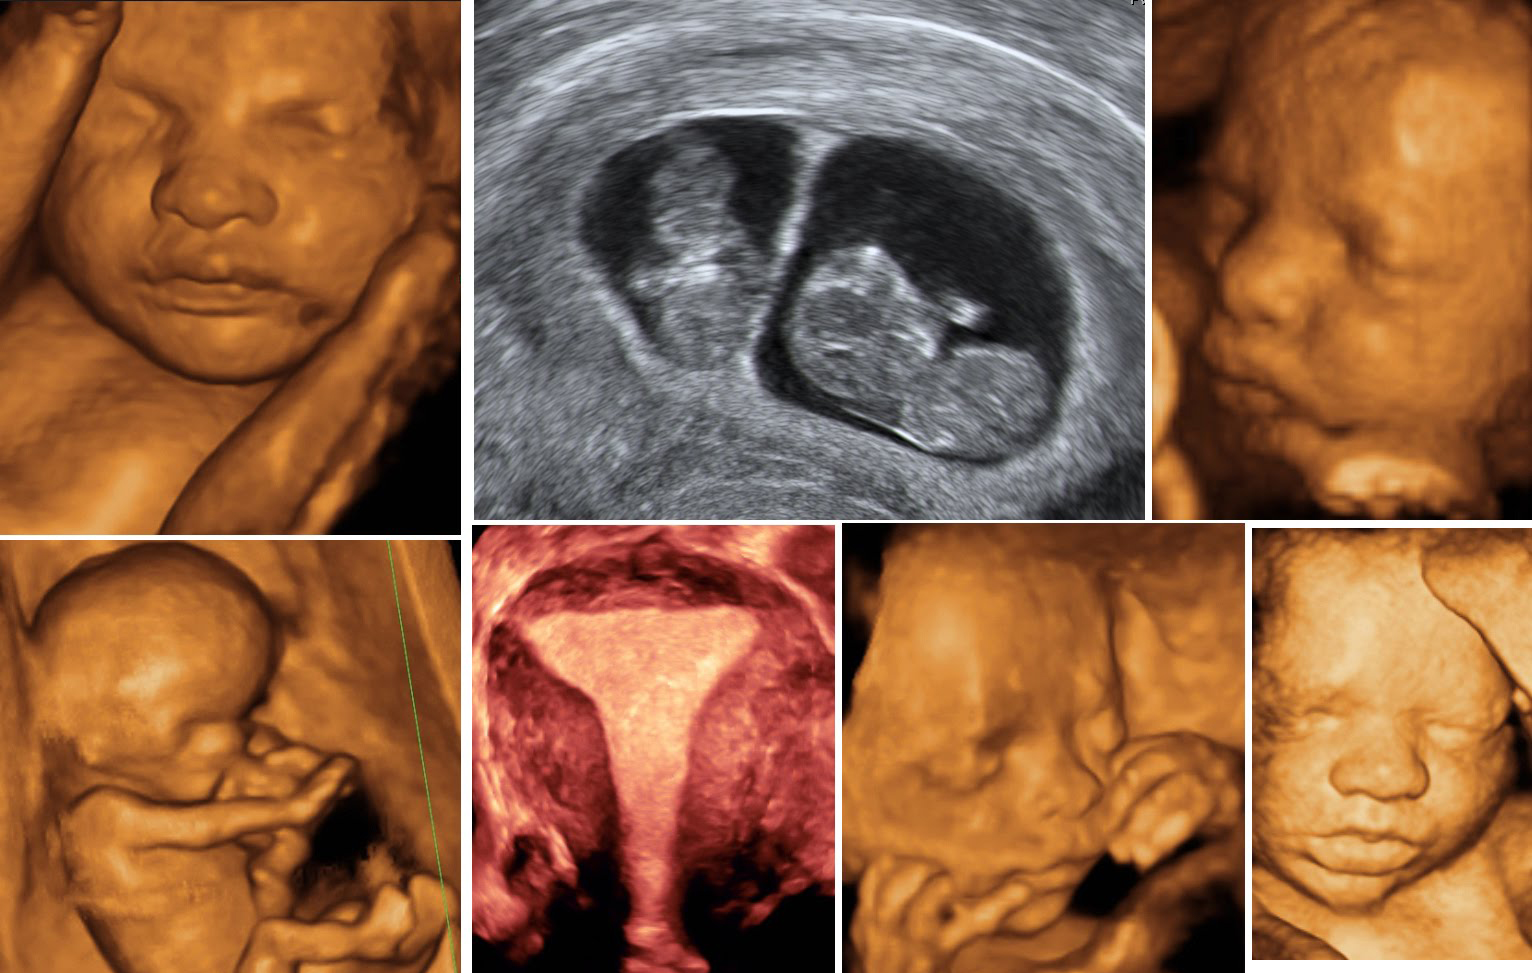

Enter the Obstetric Color Doppler, a revolutionary tool in prenatal care. This advanced sonography service is designed to provide in-depth analysis of fetal health, offering a window into the womb that standard ultrasounds might not fully capture. For Priya and mothers like her, the Obstetric Color Doppler wasn't just a medical procedure; it was a beacon of reassurance.

The Obstetric Color Doppler addresses this distinct problem by providing a comprehensive view of the baby's health. It evaluates the blood flow in the fetus, placenta, and uterus, helping detect potential complications such as fetal growth restriction or placental insufficiency early on. This insight allows expecting parents to make informed decisions and take proactive measures, significantly reducing anxiety and promoting a healthier pregnancy.

For Priya, her first experience with the Obstetric Color Doppler was nothing short of transformative. The detailed images and precise data offered a clear picture of her baby's development. The radiologist explained how the blood flow to the baby's vital organs was perfect, ensuring Priya that her little one was thriving. This newfound knowledge brought Priya immense peace, allowing her to enjoy her pregnancy journey with confidence and joy.

Case studies from across India further highlight the impact of the Obstetric Color Doppler. In Chennai, for instance, Dr. Meera, a seasoned obstetrician, recalls a case where the Doppler detected a subtle abnormality in blood flow, prompting timely intervention. The early detection and subsequent management ensured a safe delivery and a healthy baby, much to the relief of the expectant mother and her family.